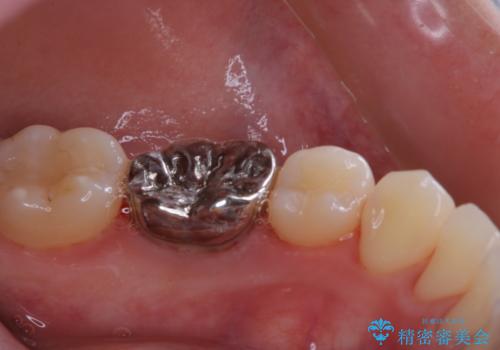

- 今後治療を進めていく予定で、まずはきれいにクリーニンングから行いたいとのことでした。PMTC60分コースを行いました。

PMTCを行う際には担当の歯科衛生士が、患者様1人1人の虫歯・歯周病などのリスク・ブラッシングスキルなどを確認します。

日々の磨き残しや唾液の成分などによりバイオフィルムや歯石はどうしても付着してしまいます。歯石や汚れを放置していると、そこで病原菌が繁殖す始めます。歯肉に炎症が生じると歯周病などの引き金となります。